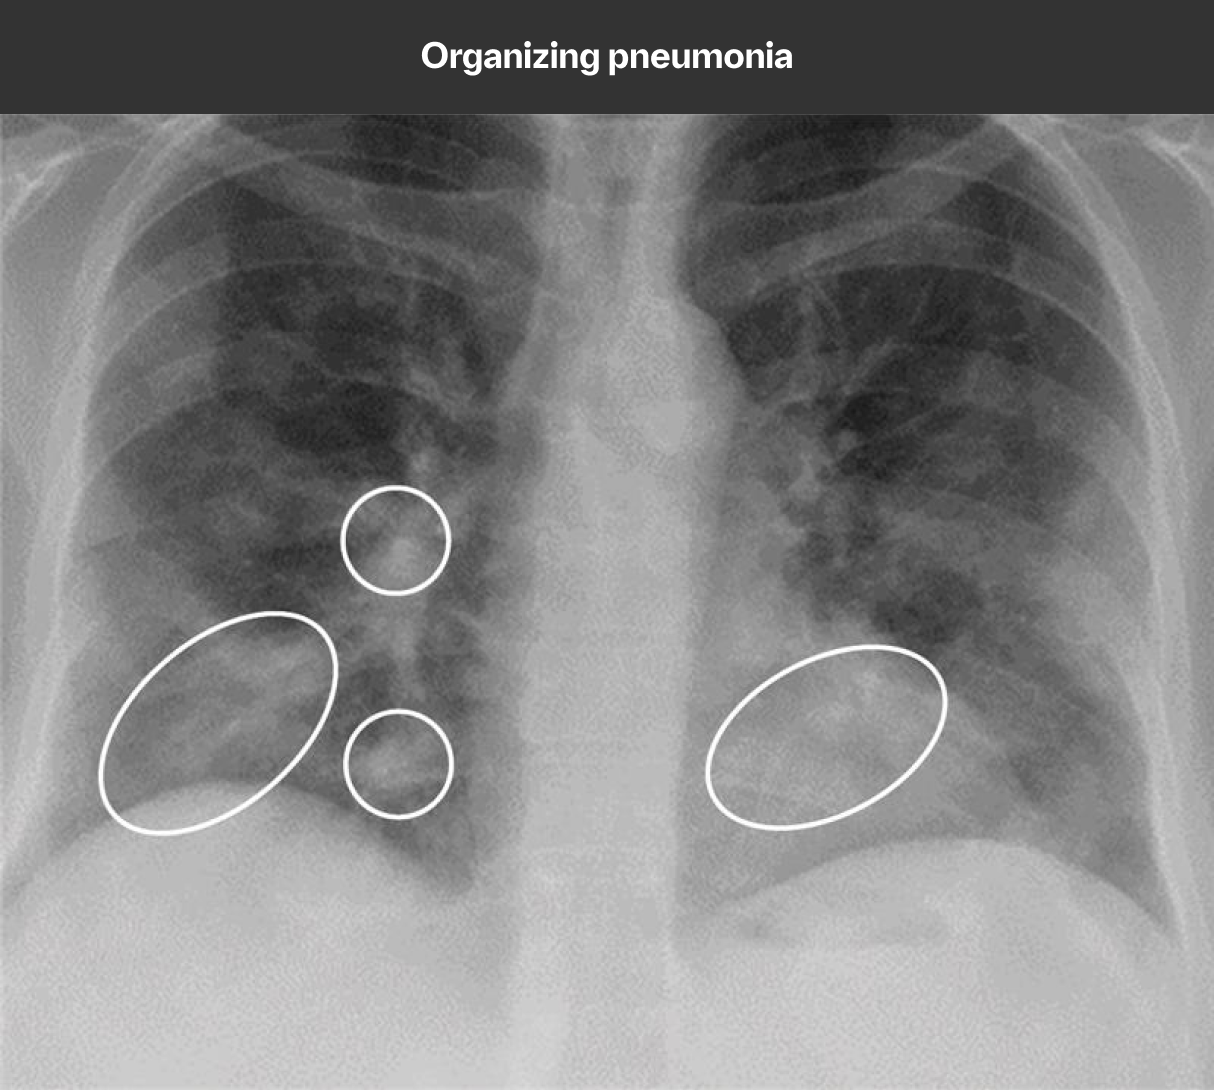

While chest x-ray is not sensitive for ILD diagnosis, it can play a role in identification9,10

Because HRCT provides a more accurate picture of the lungs than chest x-ray, it is considered the standard in diagnosing ILD. However, chest x-ray can detect pulmonary abnormalities and complications, and may even show signs of ILD prior to the development of symptoms or physiological impairment.

An abnormal chest x-ray is often the first indication of ILD

Image and case study courtesy of, and used with permission from, Lydia Chelala, MD.Findings on chest x-rays suggestive of ILD may include features of interstitial changes and/or airspace disease, such as10-12:

- Reticular lines or scarring

- Volume loss, hilar retraction, or architectural distortion

- Honeycombing

- Nodules

- Ground-glass opacification or air bronchograms

- Cysts or cystic change